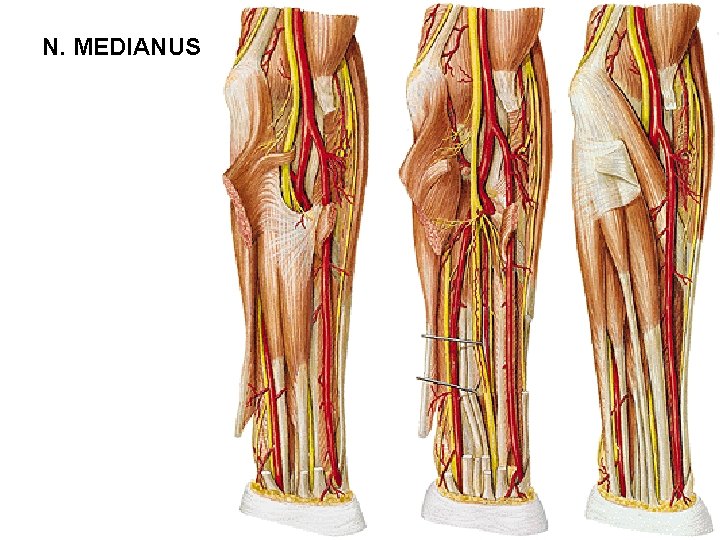

N. MEDIANUS

N. MEDIANUS

N. MEDIANUS

N. MEDIANUS - rr. articulares - rr. musculares - m. pronator teres - m. flexor carpi radialis - m. palmaris longus - m. flexor digitorum spf. - n. interosseus antebrachii ant. - m. flexor pollicis longus - radial half of m. flexor dig. prof. - m. pronator quadratus - r. palmaris